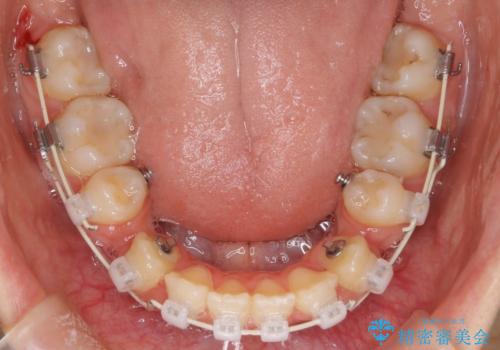

- 矯正装置

- ハーフリンガル

裏側の装置は、汚れが溜まりやすく虫歯や歯周病にかかりやすいというリスクが増加します。